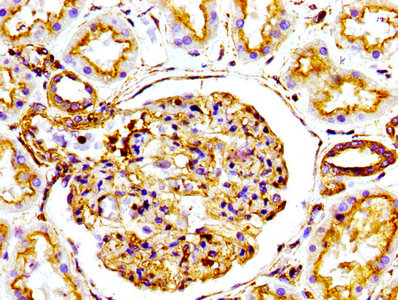

应用范围:ELISA, WB, IHC, IF, FC

Application Recommended Dilution WB 1:500-1:5000 IHC 1:50-1:500 IF 1:30-1:200 -